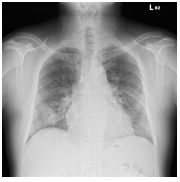

3.

9.CC: 咳嗽 4 周,有痰